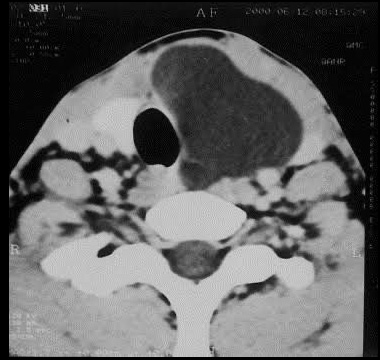

Parathyroid Adenoma

Parathyroid adenoma is a benign tumor of the parathyroid gland causing overproduction of parathyroid hormone (PTH). This leads to hypercalcemia, with symptoms like bone pain, kidney stones, fatigue, and abdominal pain. Diagnosis involves blood tests for elevated calcium and PTH levels, along with imaging studies. Treatment typically involves surgical removal of the adenoma, which usually resolves symptoms and normalizes calcium levels. Early detection and treatment are crucial to prevent complications and maintain health.